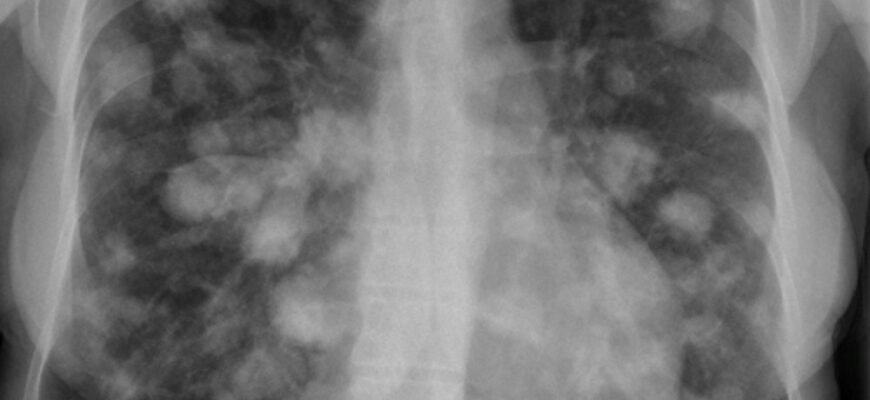

Вузли в легенях, які часто називають легеневими вузликами, є стрічковими або сферичними ділянками ущільнення у тканинах легенів. Ці утворення можуть варіювати в розмірі – від 2 міліметрів до 30 міліметрів. Важливо розуміти, що наявність вузла в легенях не завжди вказує на рак легенів; більшість вузлів є доброякісними, проте близько 40% випадково виявлених вузлів у осіб старше 50 років можуть бути злоякісними.

- Рентгенографія грудної клітини: початковий метод обстеження, що дозволяє виявити знаки вузлів;

- Комп’ютерна томографія (КТ): здатна надавати більш детальну картину та розглядати структурні зміни в легеневій тканині;